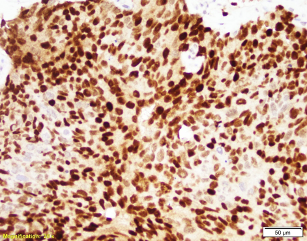

Patient is a 60-year-old male with a “bladder tumor.” Multiple nodules were present in the lung, liver and pelvic lymph nodes. A CT guided biopsy was performed, targeting the hepatic nodules. P40, synaptophysin and chromogranin are negative. MSI studies show loss of MLH1 and PMS2, with retained MSH2 and MSH6.

Picture1 WIN 20201023 14 55 38 ProWIN 20201023 14 56 49 Pro 2020-10-26T17:46:01Z

The patient has metastatic prostate cancer. Immunohistochemical stains are supportive for this diagnosis. NXK3 .1 is helpful in distinguishing poorly differentiated prostatic carcinoma from urothelial. NKX3.1 is a more sensitive and specific than PSAP. Aberrant staining of GATA 3 can be seen in subset set of prostatic carcinomas.  This potential pitfall that may be avoided with more specific and sensitive markers for prostate cancer. MSI loss may be seen in patients with prostatic cancer, however currently there is no increased risk in patients with a family history of prostatic cancer.